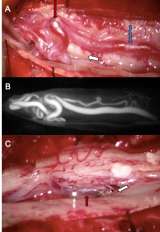

Image of Spinal Fistula Treatment

Figure 4. Spinal Fistula Treatment A) Intra-operative view of a Type 1 Spinal Dural Fistula surgery with the enlarged vein (blue arrow) laying on the spinal nerves (white arrow) is abnormally filled with red arterial blood leading to an abnormal tangle

• Surgery – many spinal vascular lesions are best treated with surgery and can be cured with low risk to the patient (Type I lesions). A spinal angiogram is typically needed prior to surgery in order to guide the surgeons to the abnormal vessels. Surgery typically involves a small incision in the back, in order to disconnect the vascular abnormality (Figure 4).